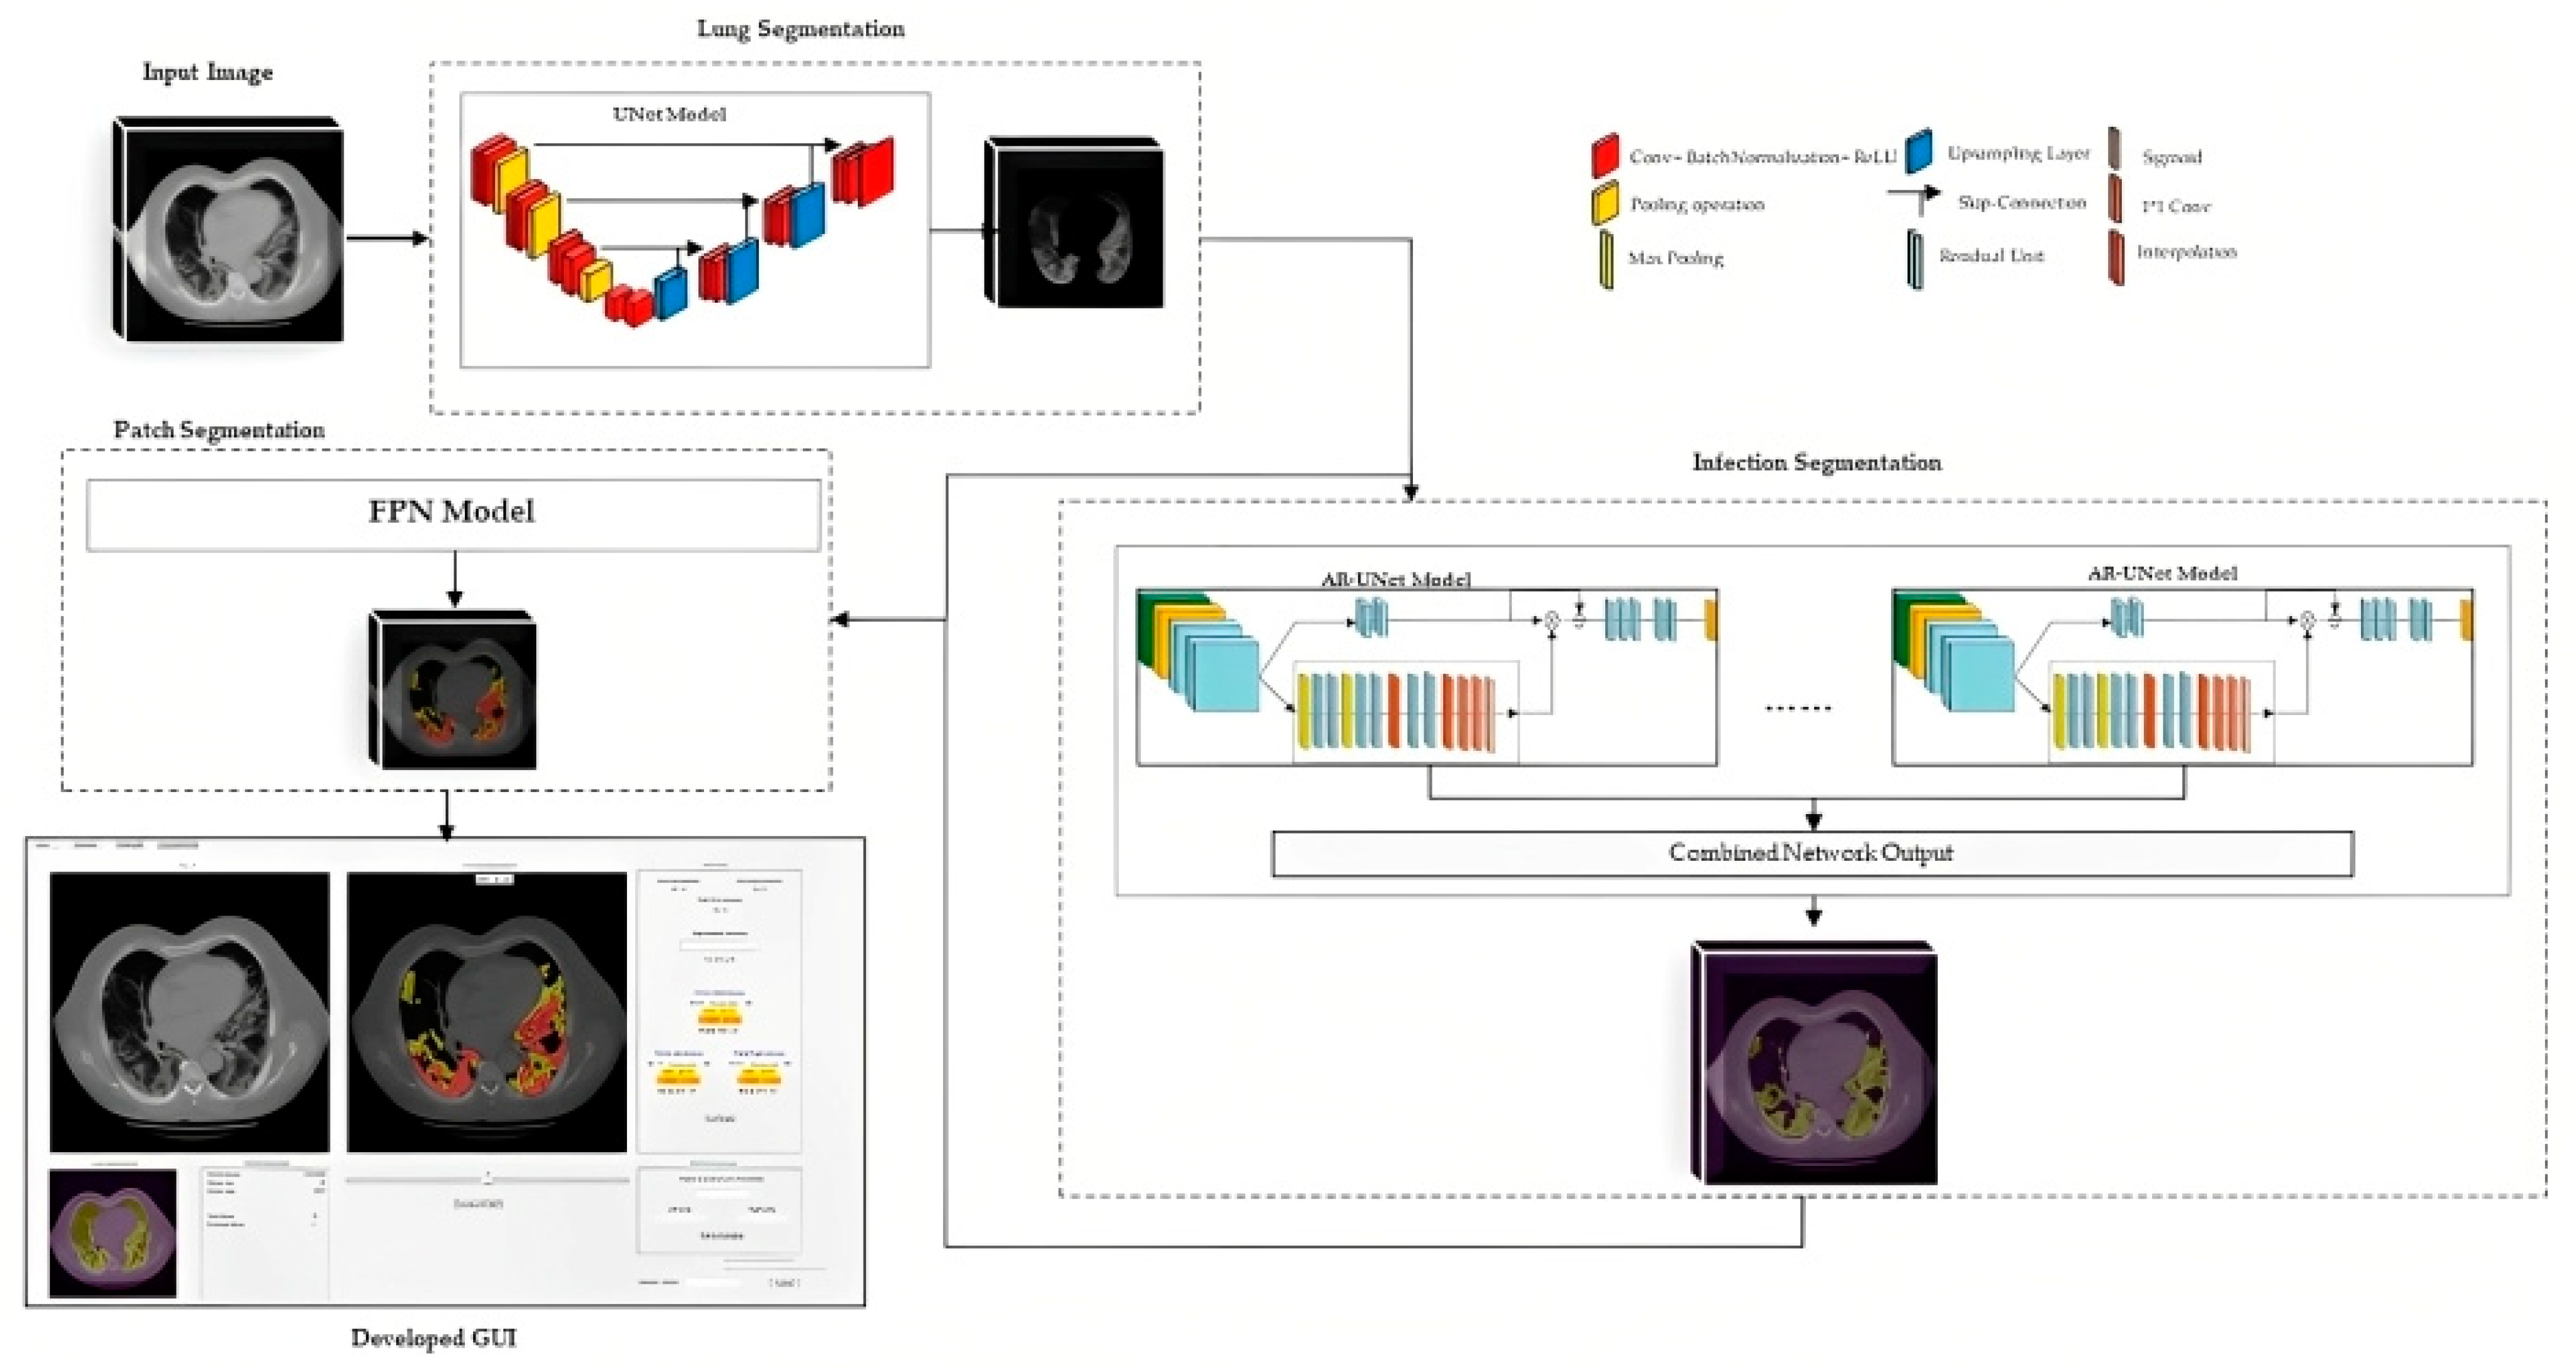

2.3. Image Segmentation Models and Output

2.3.1. Lung Segmentation

2.3.2. Infection Area Segmentation

2.3.3. Segmentation of GGO and Consolidation Patches

2.3.4. Integrated Model and GUI